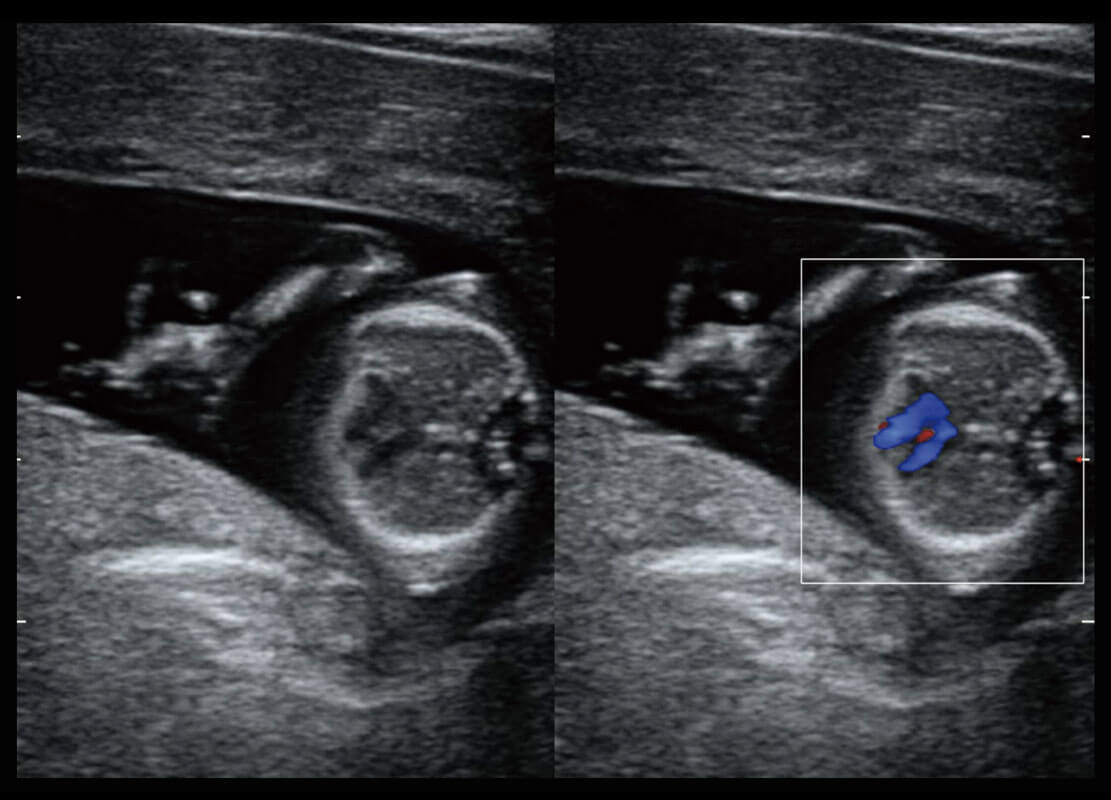

早孕-胎心

P60搭载一系列胎儿心脏成像技术,实现精细的胎儿心脏评估。

四腔切面

四腔心血流

右室双出口

胎心容积成像